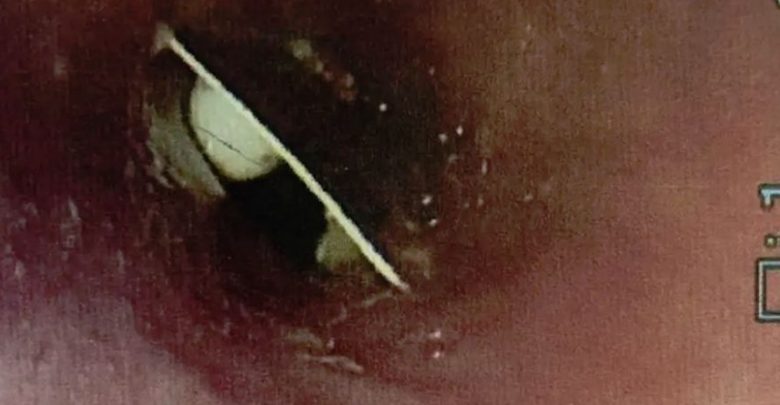

Në vizitën e saj të 4-t në spitalin Craigavon Area Hospital në Co Armagh dhe në Royal Victoria Hospital në Belfast, mjekët i bënë një kontroll me kamera dhe më në fund zbuluan misterin.

Në foto shfaqej qartë paketa e ilaçit që kishte ngecur në fytin e gruas dhe mjekët i hoqën plastikën nga fyti i gruas pas 17 ditësh. /tvklan.al